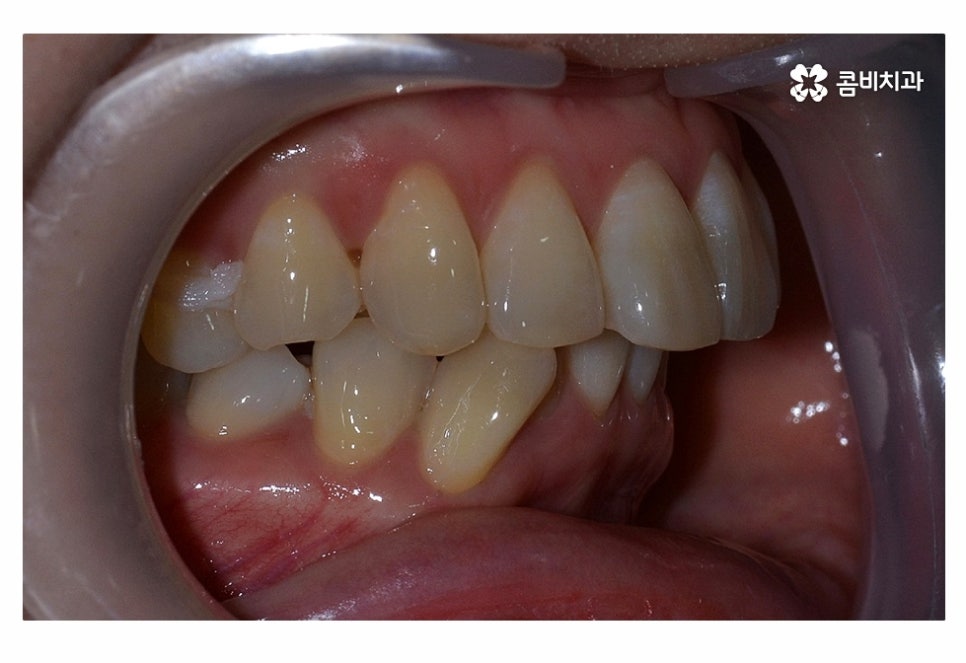

오늘 보실 교정 사례 역시도 윗니는 치아 설측교정으로

진행이 되고 아랫니는 일반적인 순측교정으로 진행되었으며

이러한 치아교정 방법을 콤비교정이라고 부르고 있어요.

위 사진에서 보시는 것과 같이 윗니의 경우 치아설측교정으로

진행이 되고 있기 때문에 교정 장치가 눈에 띄지 않고 있어요.